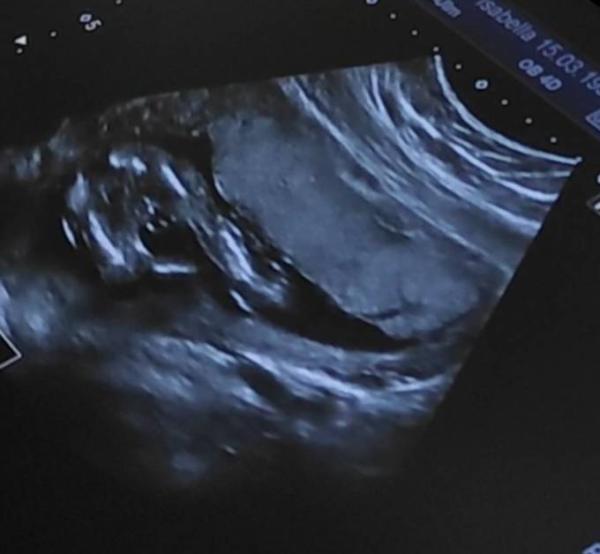

Ich war letzte Woche in der 18SSW beim Ultraschall & die Ärztin hat eine Tendenz zum Geschlecht aber möchte erst in 4 Wochen nach dem nächsten Ultraschall bekannt geben was ihre Tendenz ist, bzw das Geschlecht bekannt geben.

Ich habe ein Ultraschallbild vom Unterkörper bekommen, was mich sehr verwirrt. Im einen Moment denke ich es sieht aus wie ein Junge und im nächsten denke ich wieder es sieht aus wie ein Mädchen.

Vielleicht könntet ihr eure Meinung zum Bild äußern und mir euren Tipp abgeben

Hallo! Ich finde das Bild relativ klein pixeltechnisch aber ich denke es wird ein Junge... versuche dir im Anhang ein ähnliches Bild von meinem Kleinen hochzuladen zum Vergleich. Ich verstehe deine Neugier total! Ich wollte auch unbedingt wissen was es wird![]()

Bei deinem Bild sieht man ja definitiv einen kleinen Pullermann ![]() Freut mich sehr